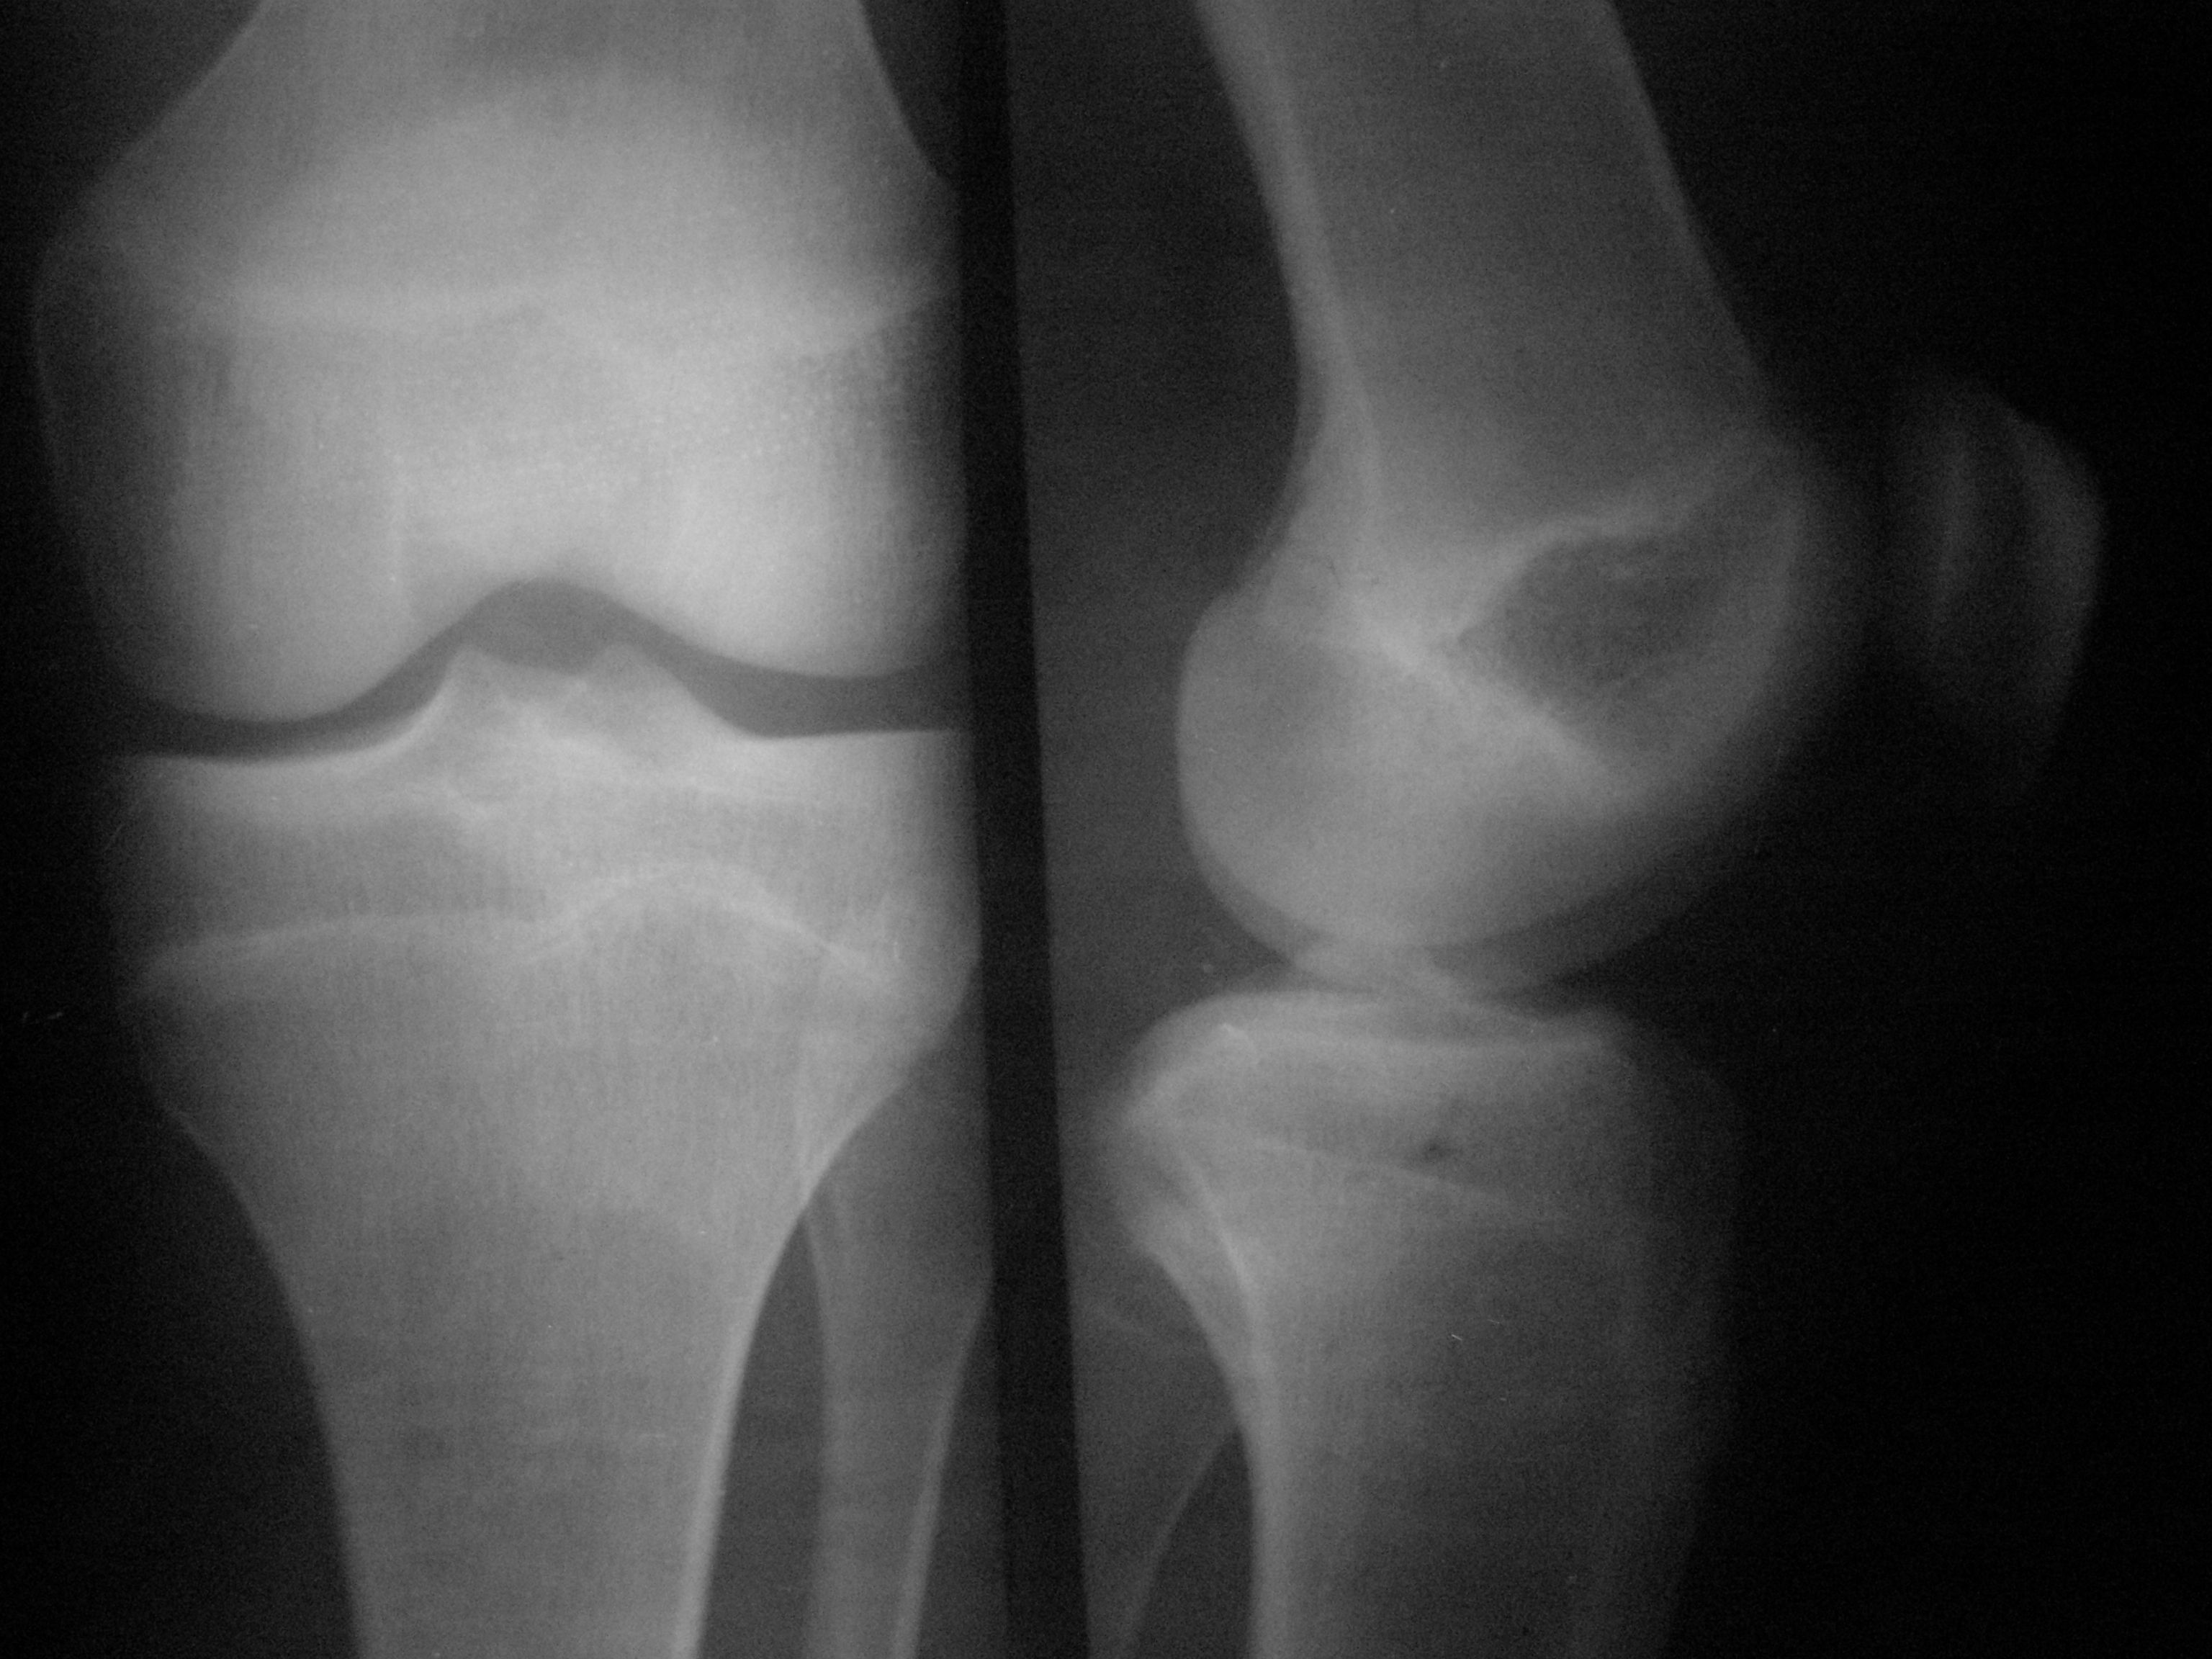

М.15лет. Жалобы на периодическую жгучую боль в L коленном суставе,после умеренной нагрузки, беспокоит 1мес. https://radiomed.ru/sites/default/files/styles/case_slider_image/public/user/15746/p4090030.jpg?itok=kvBtdL0b https://radiomed.ru/sites/default/files/styles/case_slider_image/public/user/15746/p4090031.jpg?itok=wUf85A5t ID:50918 Mon, 09/04/2012 - 17:48 #1 nelly Offline Last seen: 11 years 3 months ago Joined: 11.07.2011 - 19:19 Posts: 328 мне видится какой-то участок разряжения костной ткани в н3 диафиза БК..,не знаю как стрелочки ставить,а то отметила бы,а суставе артроз похоже имеется Mon, 09/04/2012 - 19:51 #2 ДокRg Offline Last seen: 12 years 6 months ago Joined: 30.03.2011 - 20:05 Posts: 105 nelly wrote: мне видится какой-то участок разряжения костной ткани в н3 диафиза БК..,не знаю как стрелочки ставить,а то отметила бы,а суставе артроз похоже имеется Я бы назвал этот участок разряжения - пятном Лудлофа( норма). А вот для исключения болезни Осгуд-Шляттера сделал бы снимки б/берцовых костей обеих ног с большим захватом. Mon, 09/04/2012 - 20:40 #3 maker4ik Offline Last seen: 8 years 9 months ago Joined: 19.10.2011 - 17:49 Posts: 2682 ДокRg wrote: nelly wrote: мне видится какой-то участок разряжения костной ткани в н3 диафиза БК..,не знаю как стрелочки ставить,а то отметила бы,а суставе артроз похоже имеется Я бы назвал этот участок разряжения - пятном Лудлофа( норма). А вот для исключения болезни Осгуд-Шляттера сделал бы снимки б/берцовых костей обеих ног с большим захватом. Пятно Лудлофа в эпифизе находится, а nelly про н/3 диафиза говорит. Mon, 09/04/2012 - 20:56 #4 Любовь С. Offline Last seen: 9 years 8 months ago Joined: 23.12.2010 - 01:58 Posts: 2324 Переснять диафиз в 2 проекциях. "Предоставляя весь смысл и совершенство в распоряжение одного только Бога, вы избавляете себя от бездны хлопот." Джон Уитборн. Mon, 09/04/2012 - 21:00 #5 nelly Offline Last seen: 11 years 3 months ago Joined: 11.07.2011 - 19:19 Posts: 328 да,да,я именно про это пятно,которое maker4ik указал стрелкой. Mon, 09/04/2012 - 21:17 #6 И.Бондаренко Offline Last seen: 17 hours 14 min ago Joined: 13.09.2011 - 22:55 Posts: 9209 Есть незначительное снижение медиальной суставной щели. А так бы написал норму. Tue, 10/04/2012 - 03:23 #7 Демчев Валентин... Offline Last seen: 7 years 10 months ago Joined: 08.02.2011 - 15:40 Posts: 445 Никакой болезни Осгуда-Шлаттера здесь нет. Переснять диафиз в 2-х проекциях, опять какой- нибудь метафизарный корковый дефект.

мне видится какой-то участок разряжения костной ткани в н3 диафиза БК..,не знаю как стрелочки ставить,а то отметила бы,а суставе артроз похоже имеется

Есть незначительное снижение медиальной суставной щели. А так бы написал норму.

Никакой болезни Осгуда-Шлаттера здесь нет. Переснять диафиз в 2-х проекциях, опять какой- нибудь метафизарный корковый дефект.